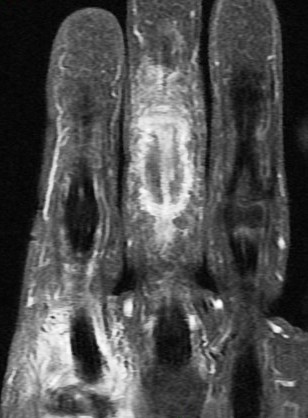

Figure 3 for case gout arthritis ( RID3567 )

Figure 3

Flexor tenosynovitis, tendon infiltration and also 2nd MCP synovitis with subtle reactive osteitis and early erosive change. My differential was RA vs gout. This is proven gout.